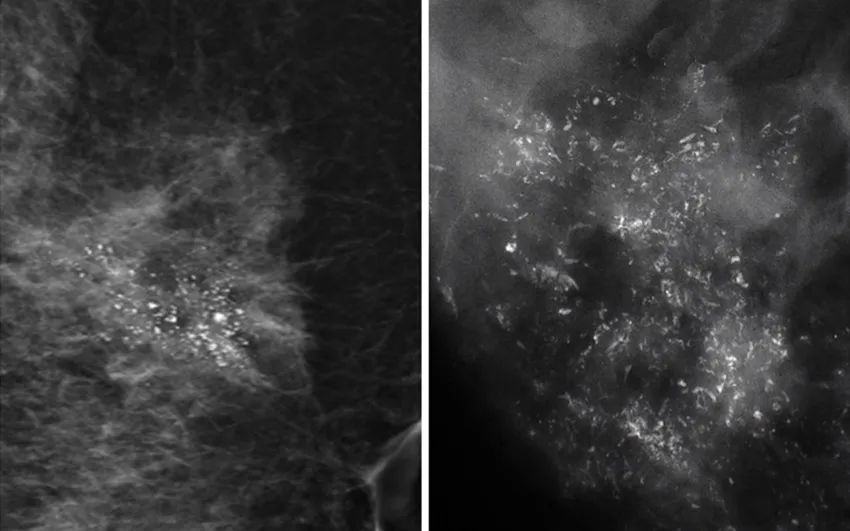

當(dāng)癌細(xì)胞不受控制地生長,這一群癌組織會變得很擁擠,導(dǎo)致里面小部分的細(xì)胞會因組織缺氧而壞死。這時,我們身體無法清除壞死的組織,這些細(xì)胞就變硬而形成鈣化點。

因此,惡性鈣化點的特點是:聚集很緊密,簇聚于局部區(qū)塊,且鈣化點很小,形狀不規(guī)則,每個點都不太一樣,或有針尖狀、小桿狀、分叉狀、簇狀及泥沙樣多屬于惡性病變。